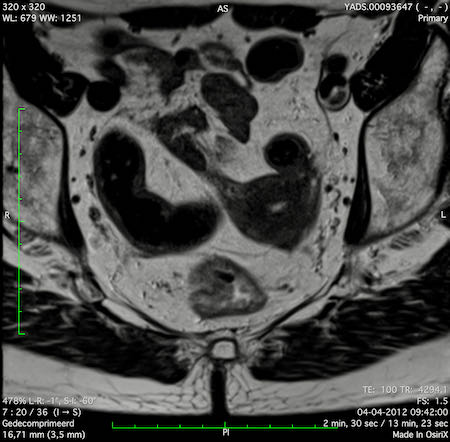

Hình ảnh

Các hình ảnh được cung cấp cho thấy ung thư biểu mô tế bào nhẫn với tình trạng dày lan tỏa thành trực tràng, hình ảnh bia bắn điển hình, và sự xâm lấn mỡ mạc treo trực tràng.